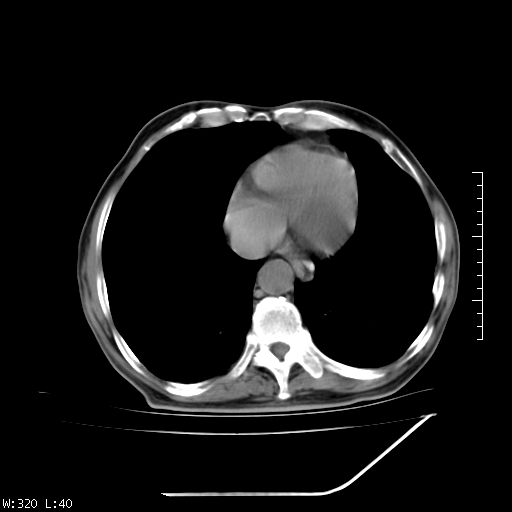

标题: CT23994:男、72、咳嗽、气短两月余,近来消瘦。 [打印本页]

标题: CT23994:男、72、咳嗽、气短两月余,近来消瘦。

右上肺实变,与胸膜关系密切,右肺容积缩小,隆突下淋巴结增大,考虑1 肺结核 2 肺癌

右上肺大片状密度增高影,与胸膜关系密切,内见低密度透亮影,胸膜下可见三角形不张影,左下肺沿支气管走形结节影,纵膈内淋巴结显示。考虑结核并疤痕性不张可能性大,建议穿刺活检,排除肺泡癌。